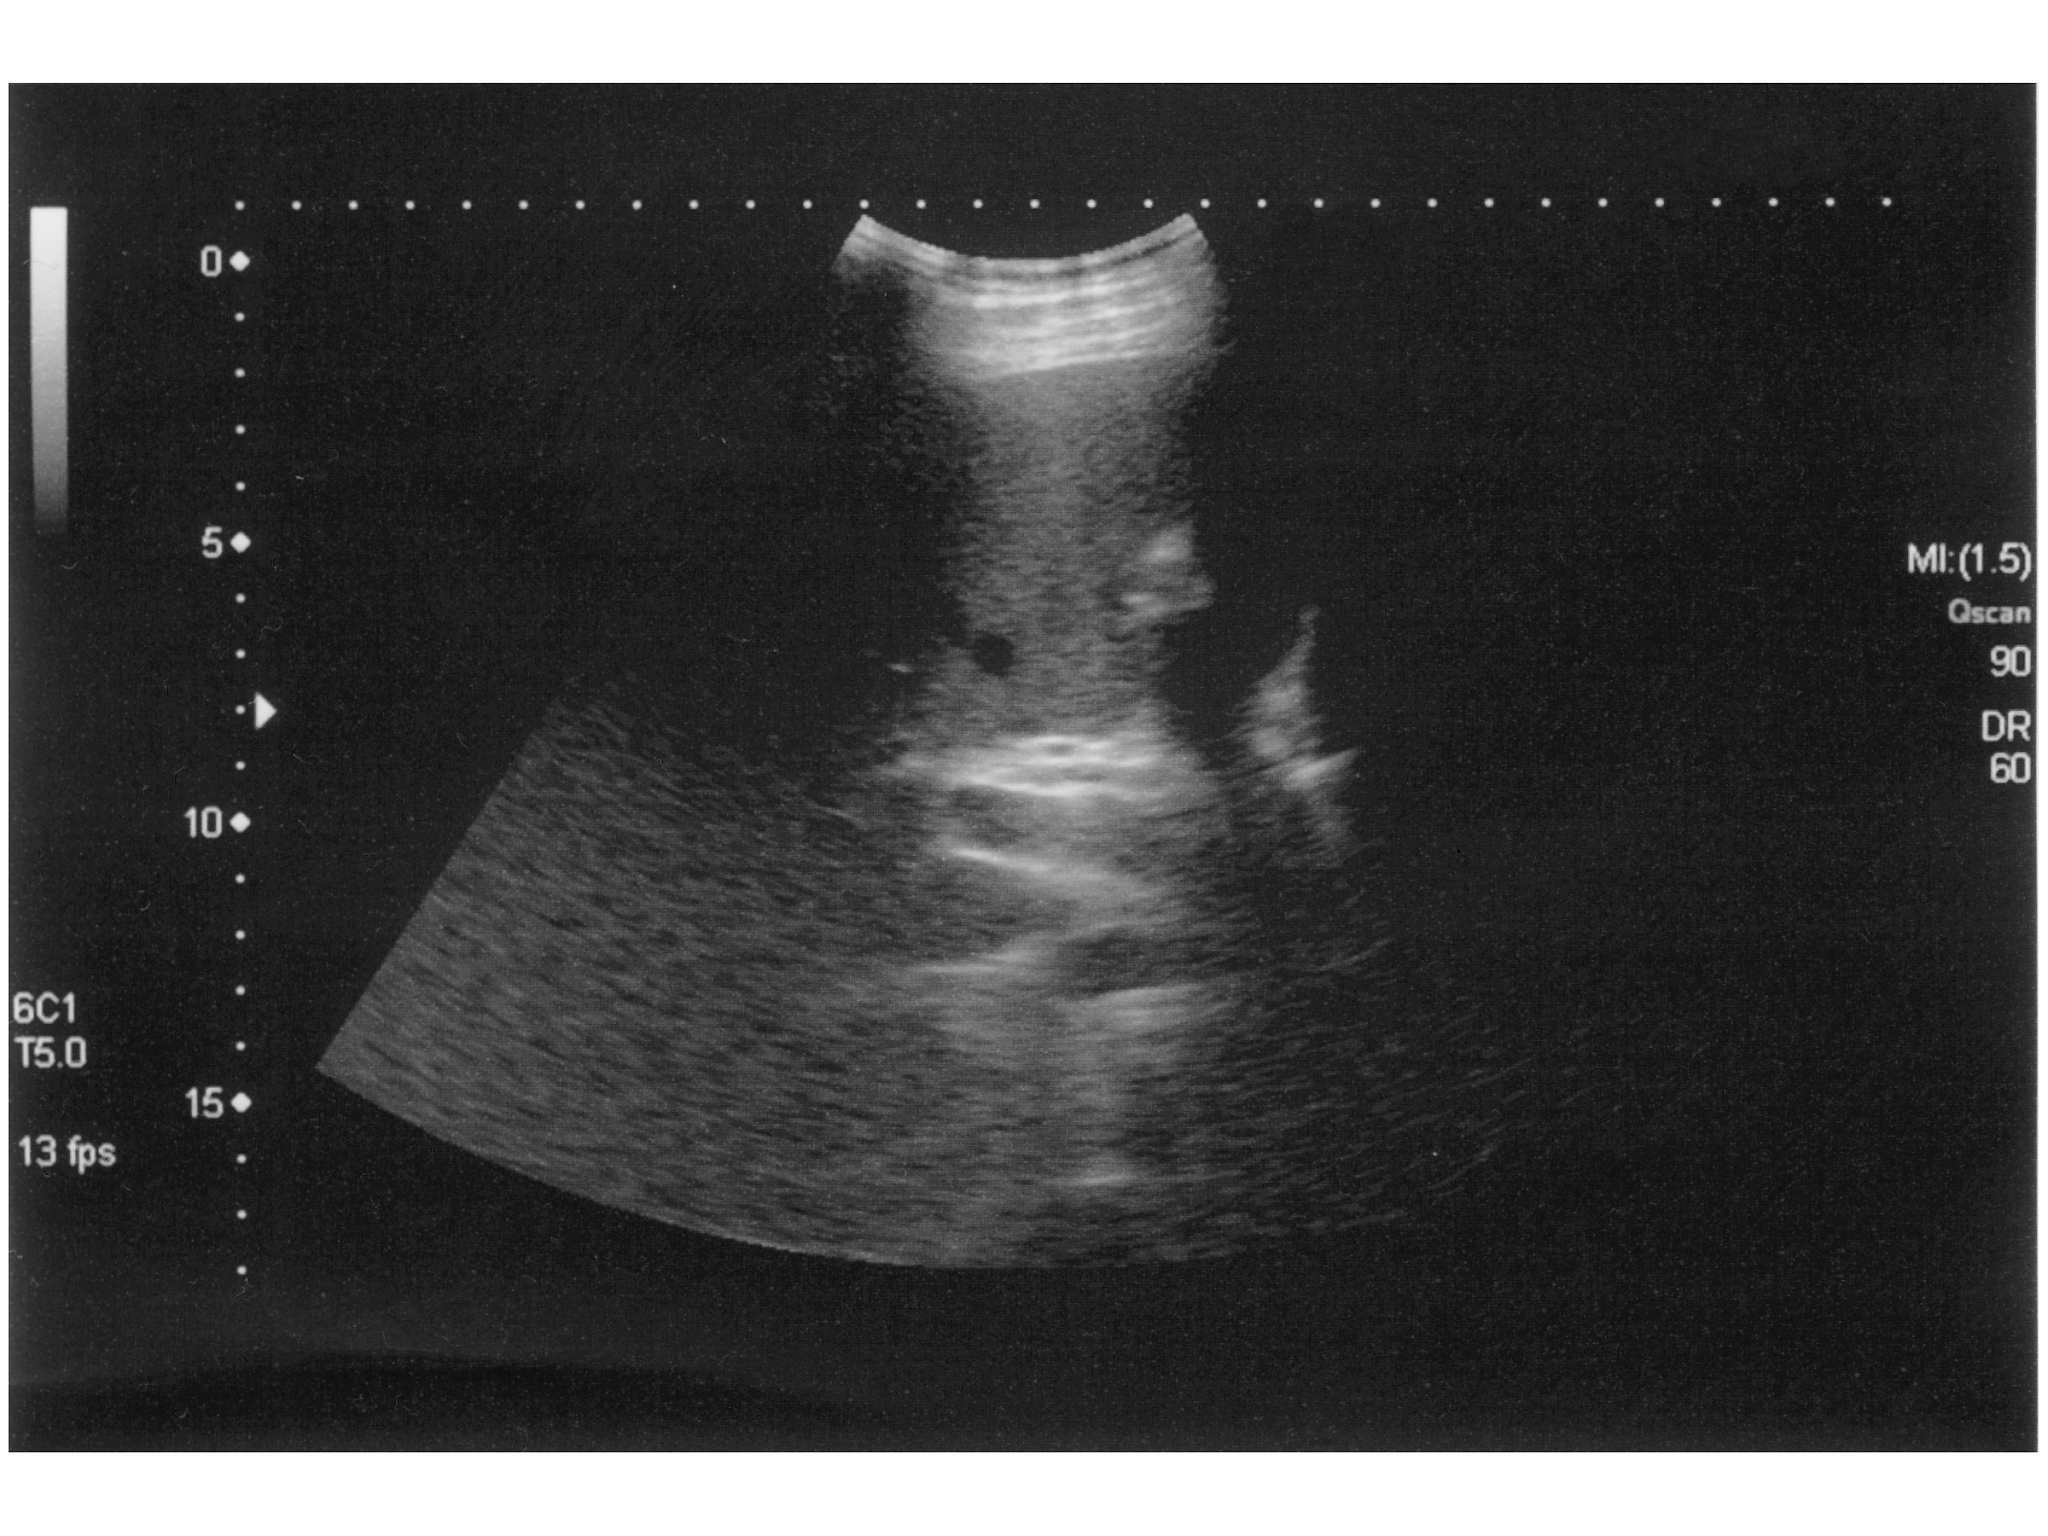

腔内超声造影是一种新型的超声影像技术,它通过将微泡造影剂注入腔内,利用微泡对超声波的反射增强信号,从而提高超声图像的清晰度和分辨率,帮助医生更准确地诊断胆管疾病。

• 提高诊断准确性:腔内超声造影可以更清晰地显示胆管的形态、结构和病变,有助于医生更准确地诊断胆管疾病,如胆管结石、胆管狭窄、胆管肿瘤等。

• 胆管结石:腔内超声造影可以更清晰地显示胆管结石的形态、大小和位置,有助于医生更准确地诊断胆管结石,并制定最佳的治疗方案。

• 胆管狭窄:腔内超声造影可以更清晰地显示胆管狭窄的程度和范围,有助于医生更准确地判断狭窄的严重程度,并制定最佳的治疗方案。

• 胆管肿瘤:腔内超声造影可以更清晰地显示胆管肿瘤的形态、大小和位置,有助于医生更准确地诊断胆管肿瘤,并制定最佳的治疗方案。